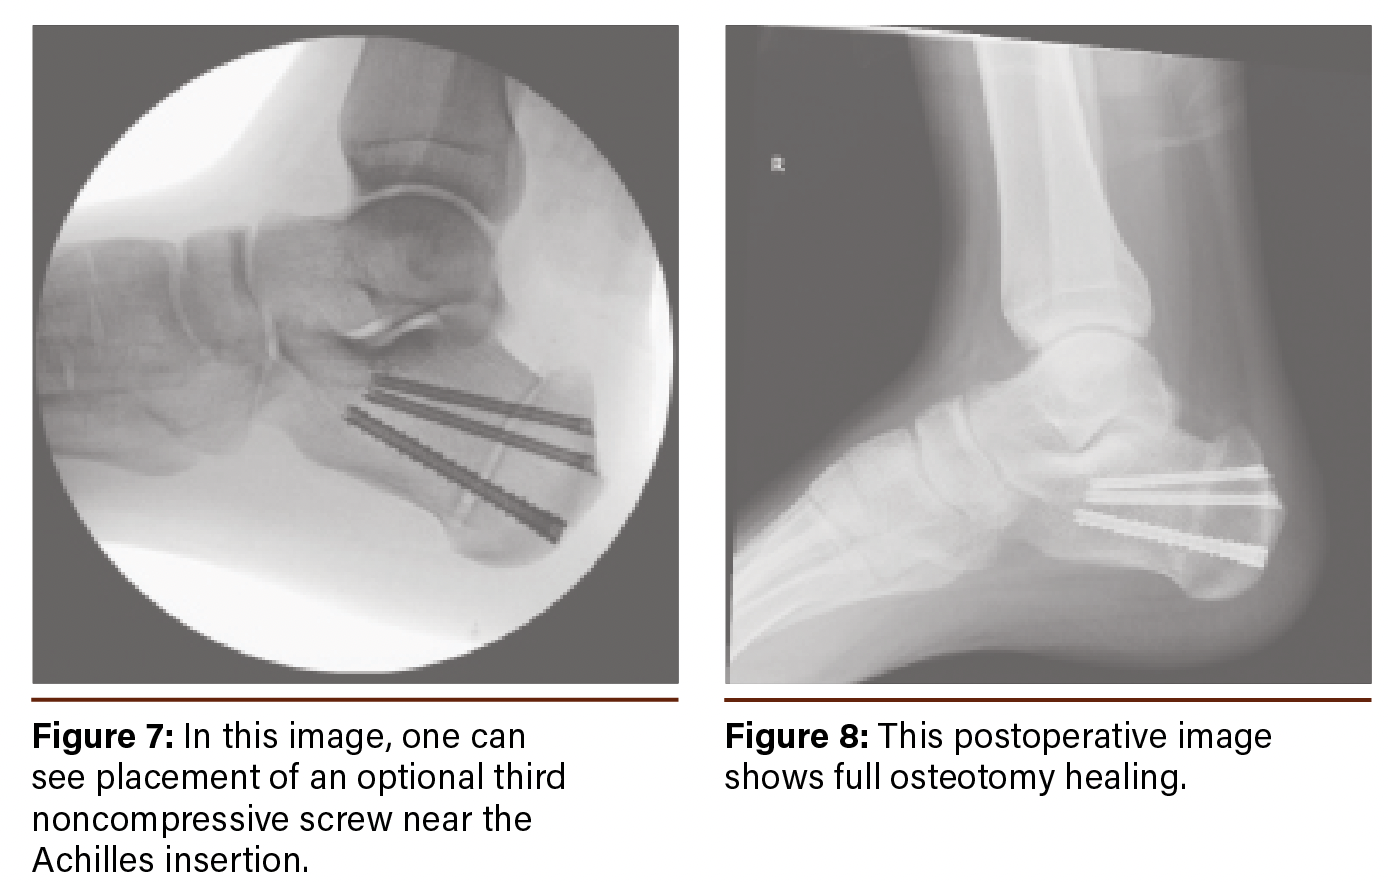

We then insert a minimally invasive surgical burr to create a closing wedge osteotomy (Figure 4). The posterior and anterior arms of the wedge are created first with no attempt to eliminate the bone. Once we are satisfied with the arms of the wedge, we proceed with a combination of a wedge and straight-cutting burr to pulverize the medullary content within the wedge. This takes place with continuous irrigation to minimize thermal injury. Throughout, we take care to leave a 5-8mm plantar hinge at the apex of the osteotomy. Then, we reduce the osteotomized segments by gentle dorsiflexion of the foot, allowing it to hinge on the plantar cortex before placing 2 cannulated screws from posterior to anterior (Figure 5). Additionally, we often place a third noncompressive screw for patients with a larger body habitus near the Achilles tendon insertion for added stability (Figures 6 and 7).